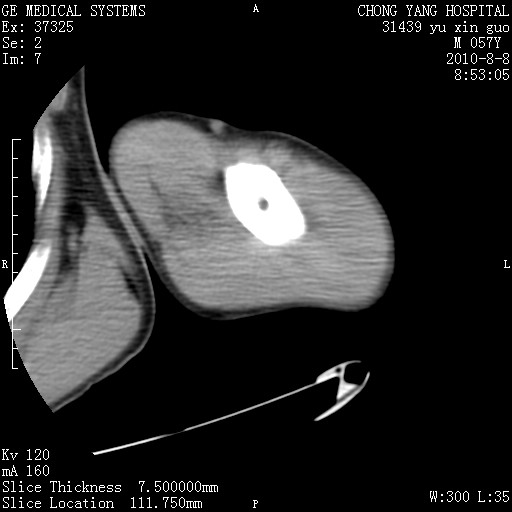

标题: CT28267:M57Y 上臂包块8年余。 [打印本页]

标题: CT28267:M57Y 上臂包块8年余。

典型脂肪瘤改变

上臂软组织内脂肪瘤。

包膜光滑、完整的脂肪密度肿块,支持脂肪瘤。